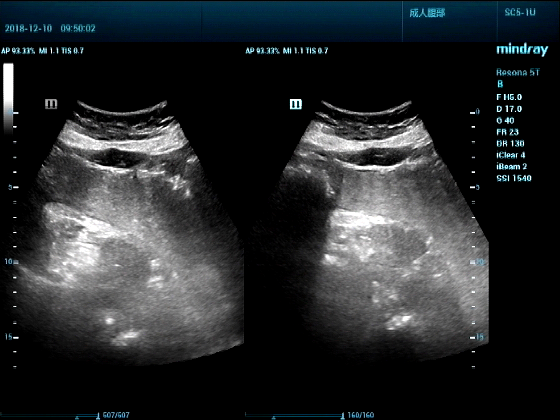

病例一:女,53岁,胃部不适一周来诊

超声可见:胃腔内见一小鸡蛋大强回声团块,后方伴强声影,位置活动。

问及病史吃山楂,柿子。

超声提示:结合临床考虑胃结石,治疗后复查